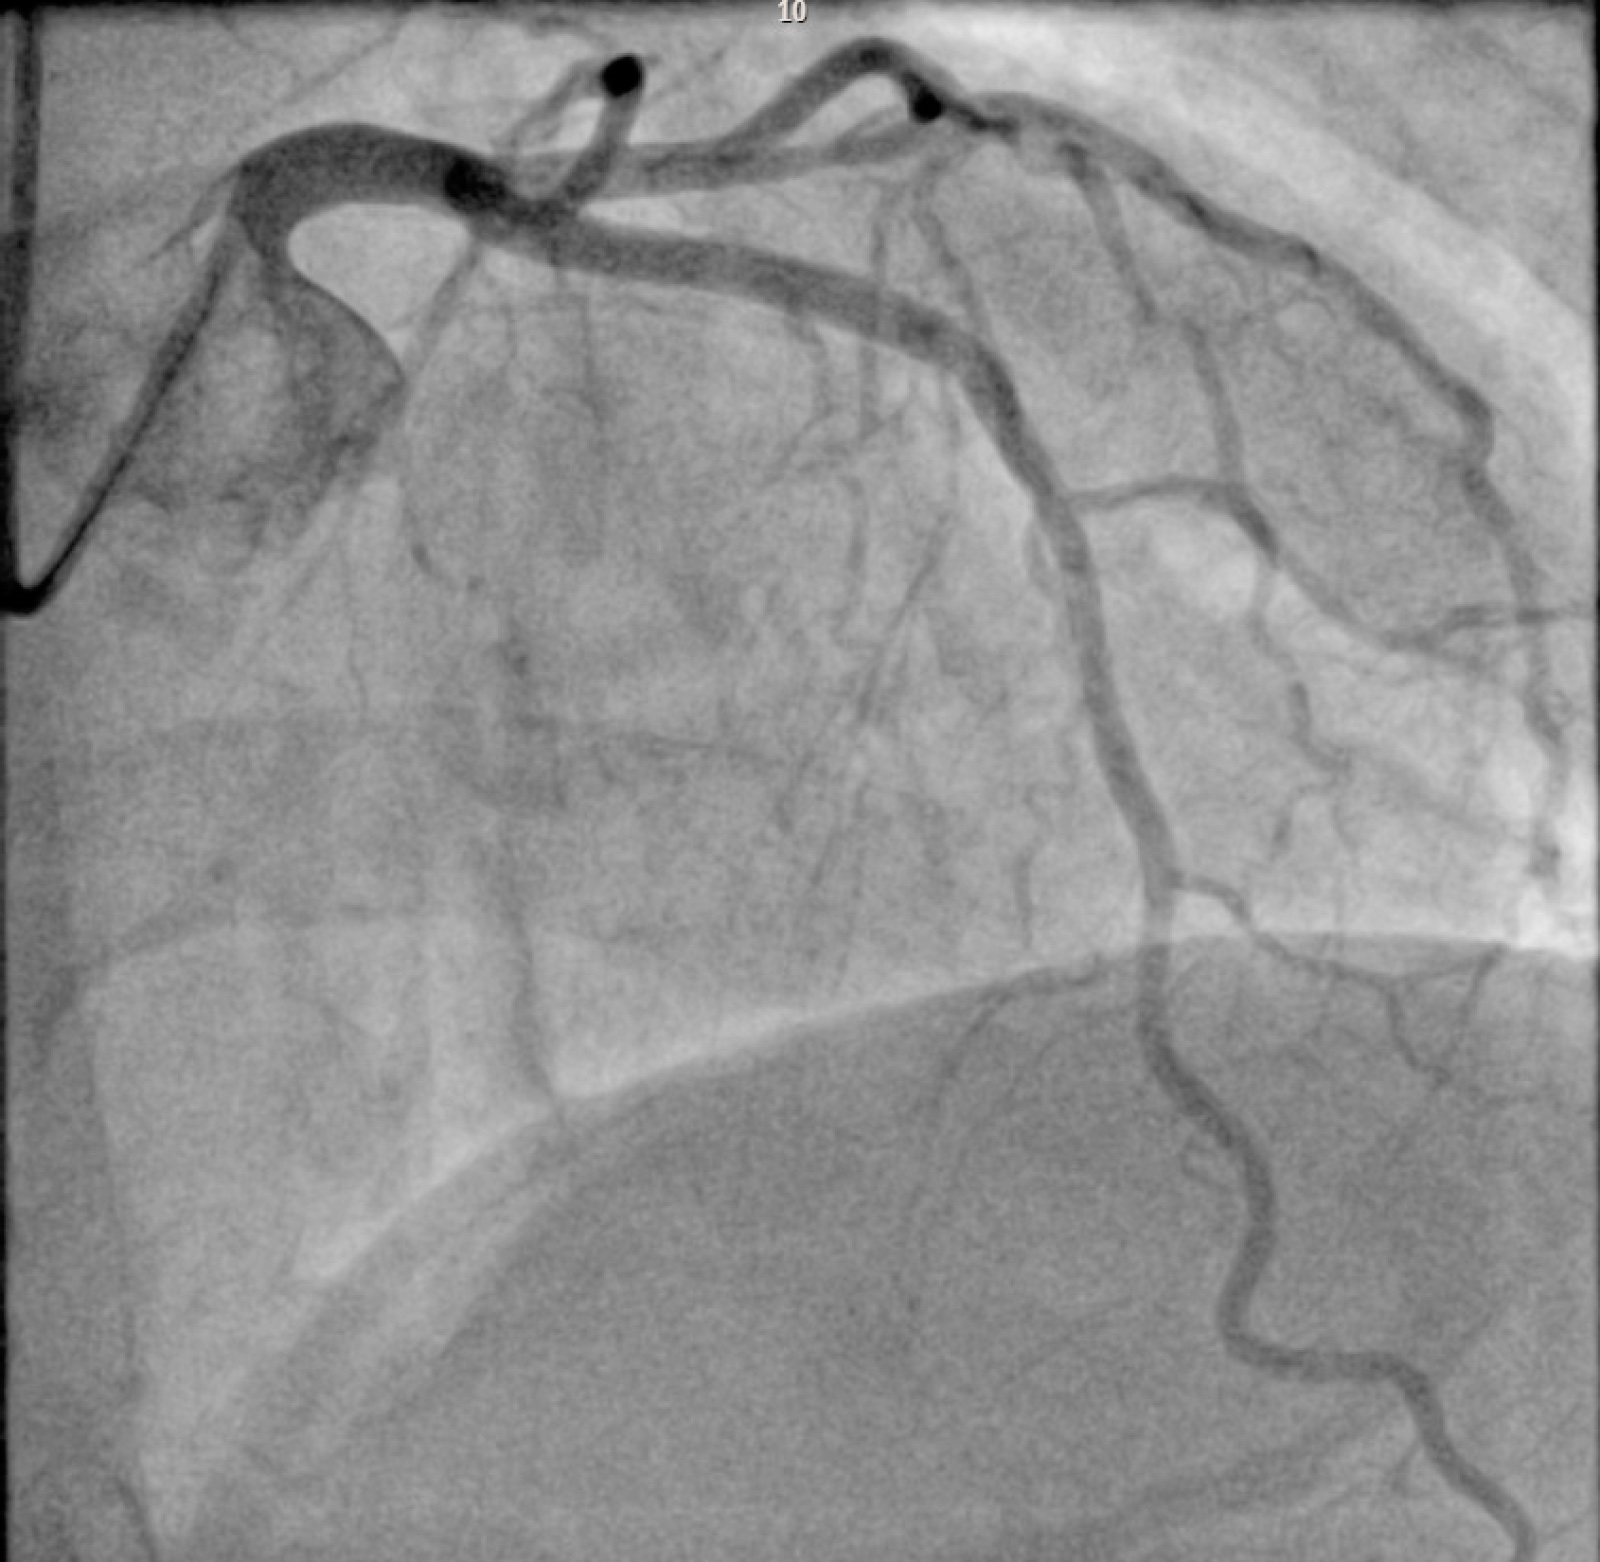

There was excellent angiographic and IVUS result with a distal minimal stent area of (MSA) 9.1 mm2 and stent expansion (SE) of greater than 90%.

- Post PCI LAD Angiogram